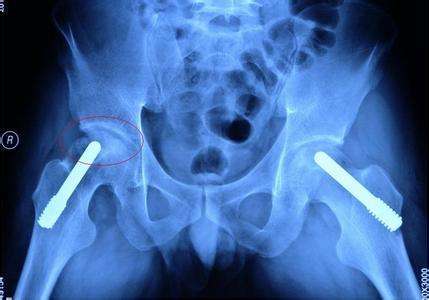

股骨头坏死患者肌肉萎缩主要是因为大腿的血液供应减少造成的。股骨头坏死的发生虽然原因各个有不同,但是发病肌机理都是导致股骨头周围血液循环障碍。

血液循环障碍不但会造成股骨头坏死,同时还会造成骨动脉都下肢广泛组织的血液供应减少,下肢肌肉长时间营养不良,就会造成下肢肌肉萎缩。第二种原因是,患肢大腿由于疼痛不经常走路负重,肌肉长时间得不到有效的锻炼肌肉不再发育,肌肉逐渐萎缩变小,造成的废用性肌肉萎缩。